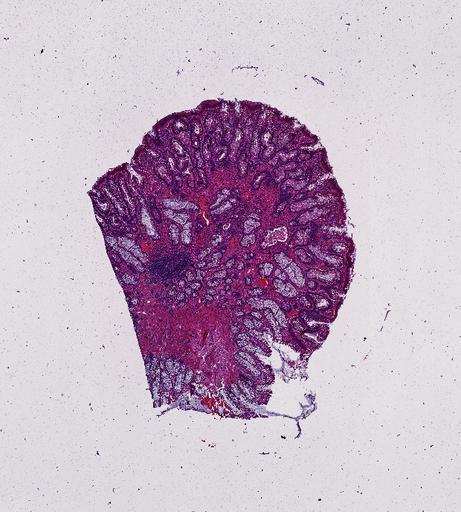

High‑resolution three‑dimensional (3D) tissue atlases promise to redefine how we study cellular architecture‑function relationships in human tissues. Large-scale consortia such as the Human Bimolecular Atlas Program (HuBMAP) systematically build detailed 3D organ maps by profiling serial tissue sections with single-cell spatial technologies. However, an accurate and efficient reconstruction method that can handle atlas-scale datasets remains elusive. We introduce Space-map, an open-source method that integrates single‑cell coordinates with optional histological image features to assemble serial sections into 3D models. Space‑map combines multi‑scale feature matching with large‑deformation diffeomorphic metric mapping, delivering global reconstructions while preserving local micro‑anatomy. To demonstrate the capability of Space-map, we generated a serially sectioned spatial transcriptomics (Xenium, ~2.9M cells) dataset and a spatial proteomics dataset (CODEX, ~2.4M cells). Applying Space-map to these single-cell spatial maps, we built three 3D models for both diseased (colon polyp) and reference colon tissues. These high-resolution 3D models showcase the intricate structure of the human colon across different states. Space-map is fast and highly efficient. We demonstrated its performance and accuracy using in‑house and public datasets. The result shows that Space‑map is 10 times faster and ~2‑fold more accurate than PASTE and STalign, making 3D atlas reconstruction more accessible. Our study provides a new robust and user-friendly software available at https://github.com/a12910/spacemap that can be easily applied for constructing molecular 3D tissue maps of human organs at single-cell resolution.